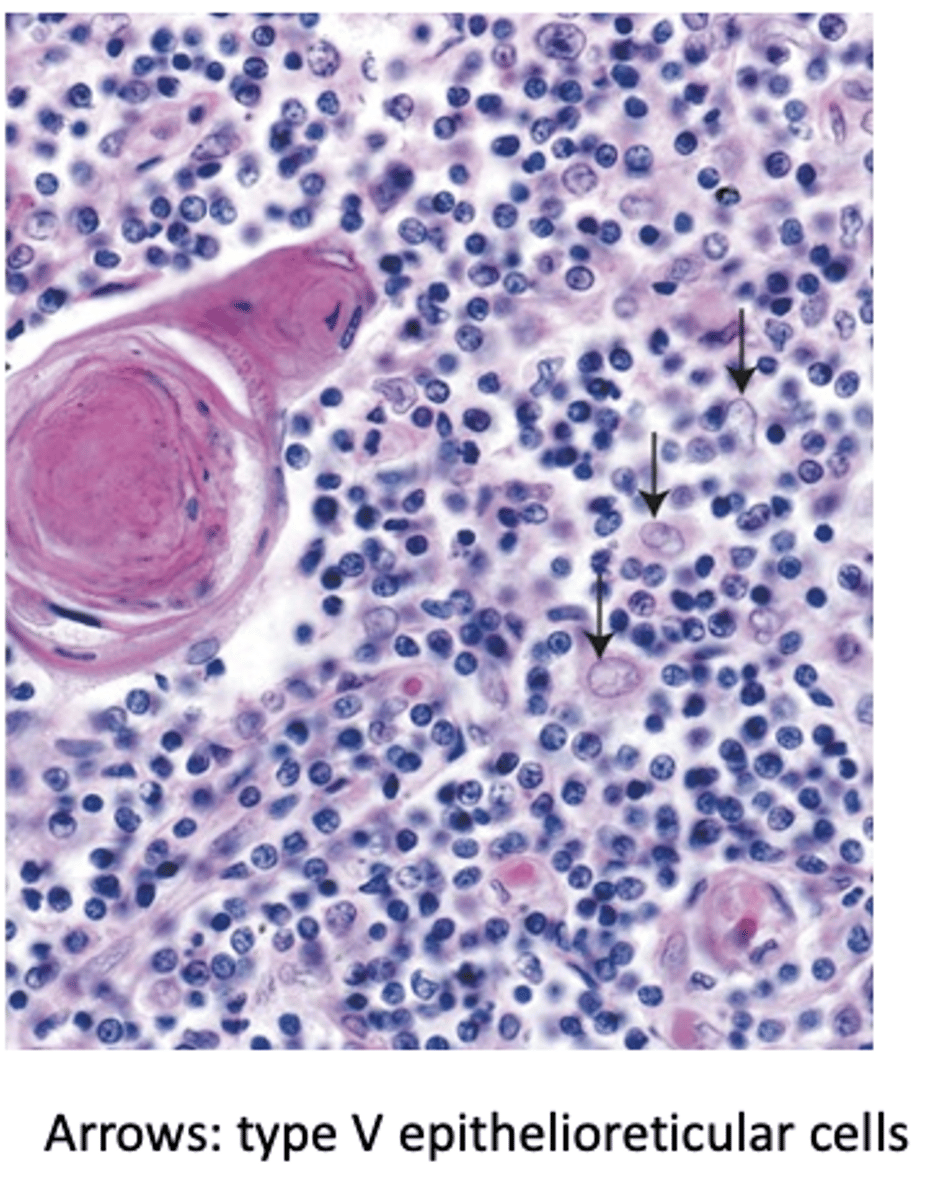

What are the three types of medullary thymic epithelial cells (TECs) present in the thymic medulla?

1. Type IV epithelioreticular cells

2. Type V epithelioreticular cells

3. Type VI epithelioreticular cells

What distinctive structures are found in the thymic medulla?

Hassall’s corpuscles.

What are Hassall’s corpuscles made of?

Isolated masses of concentrically arranged type VI TECs.

Where are Type V epithelioreticular cells located in the thymus?

Throughout the medulla.

How are the processes of Type V epithelioreticular cells connected?

By desmosomes

What structure do Type V epithelioreticular cells form?

A cytoreticulum.

Which cells are supported by the cytoreticulum formed by Type V TECs? (3)

T lymphocytes, dendritic cells, and macrophages.

What unique function do Type V epithelioreticular cells perform beyond the thymus?

They express specialized proteins that affect other organs

What is the role of Type V epithelioreticular cells in thymic organization?

They compartmentalize groups of lymphocytes.